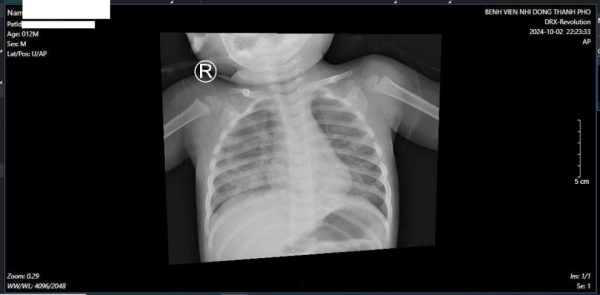

Hình ảnh X quang ngực lúc nhập viện cho thấy tình tổn thương phổi lan tỏa 2 phế trường bên phải nhiều hơn bên trái, gây suy hô hấp nặng